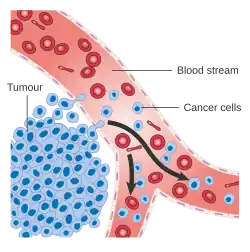

CNS metastasis is the spread and proliferation of cancer cells from their original tumour to form secondary tumours in portions of the CNS.[1] Typically, this progression initiates when tumour cells separate from the primary tumour and insert into the bloodstream or the lymph system via intravasation.[2] Intravasation into the circulatory system allows the tumour cells to travel and colonise distant sites such as the brain, a major structure of the CNS, forming a secondary brain tumour.[2] However, CNS metastasis only occurs when genetically unstable cancers can adapt to foreign tissue native to the CNS environments, but dissimilar from the original tumour.[3] Subsequently, metastasised cells assume new genomic phenotypes, while dropping unfavourable characteristics, once cells disassociate from the primary lesion.[4] This is particularly crucial for the formation of CNS metastasis, as the tumour cells require characteristics favourable for the disruption of the blood-brain barrier, allowing them to transverse.[5][6]

Recent evidence demonstrates that the dissemination of cells from the primary tumour is not sequential but consists of overlapping processes and routes.[4] This includes the tumour cells invading and colluding with tissue stroma while adapting to evade immune surveillance by suppressive inhibition of regular cellular anti-tumourigenic properties.[4] These cancerous cells modulate the foreign tissue environment while evolving to adapt to therapeutic intervention.[4]